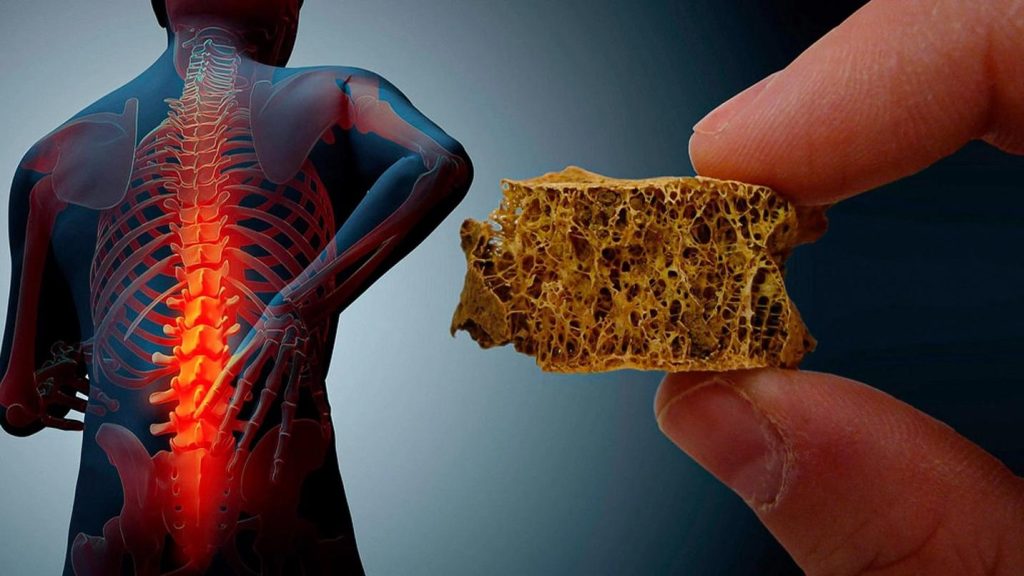

بهترین دکتر پوکی استخوان اهواز + لیست 10 تایی